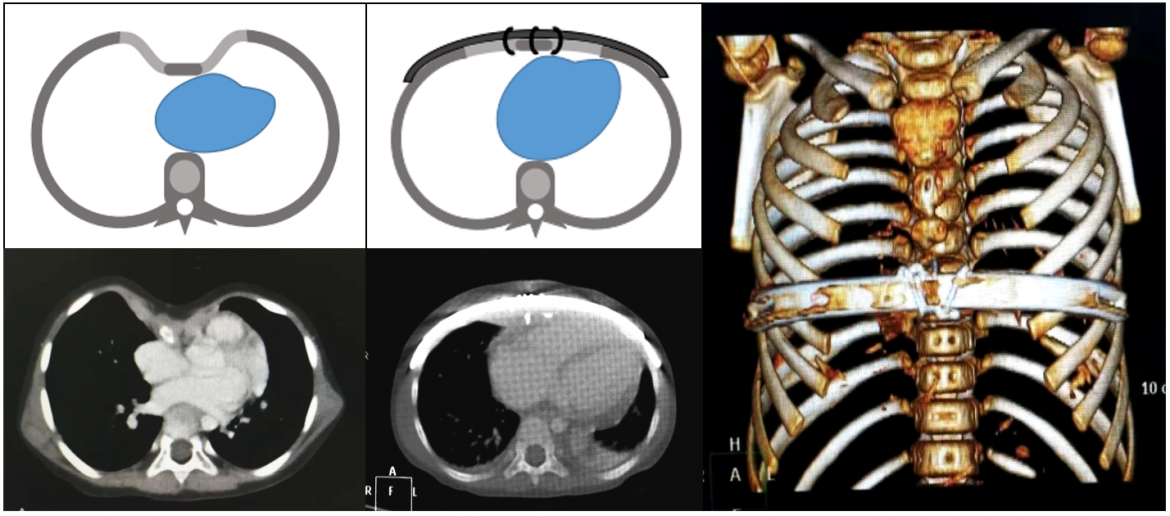

The Wang procedure, pioneered by Dr Wenlin Wang in 2018, revolutionized the treatment of pectus excavatum. Unlike the traditional Nuss procedure, which involves inserting bars into the chest cavity, the Wang procedure places a bar on the surface of the concave sternum, minimizing trauma and eliminating the risk of cardiac injury. This method is especially advantageous for younger patients, including those under the age of 5, and offers a quicker recovery with less recurrence of deformities.